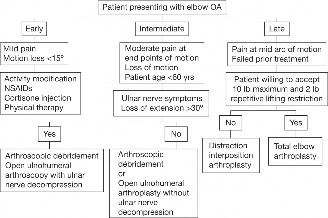

A 45-year-old carpenter presents with shoulder pain that has been ongoing for the last 3 months. He denies any significant injury. He describes night pain and significant discomfort at work. His imaging is shown in Figure 2–9. What is the most likely diagnosis?

Figure 2–9_From Shi LL, Mullen MG, Freehill MT, et al. Accuracy of Long Head of the Biceps Subluxation as a Predictor for Subscapularis Tears. _Arthroscopy 2015;32(4):615–619.

Discussion

The correct answer is (A). Medial subluxation of the biceps tendon as seen in this MRI is commonly associated with a tear of the subscapularis tendon which attaches to the lesser tuberosity. This patient’s pain may in part be attributable to the subscapular tear and this should be evaluated for during physical examination. Supraspinatus tears (Answer B) cannot be easily visualized on axial views and are not associated with medial biceps subluxations. A labral tear and ALPSA lesion (Answers C and D) are not seen on the images provided. The question stem and MRI are not suggestive of shoulder instability (Answer E). Objectives: Did you learn...? Diagnose and treat acute rotator cuff tears?